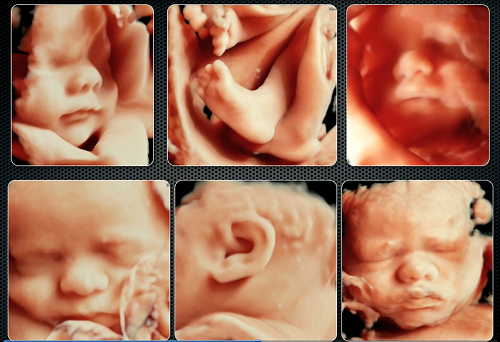

Siêu âm 3D

Siêu âm 3D tạo ra một loại hình ảnh 3 chiều của thai nhi. Giúp cho các bậc cha mẹ có thể nhìn thấy con như thật và cảm thấy gần gũi hơn với con. Ngoài ra, phương pháp này cũng giúp cho các bác sĩ có thể đánh giá sức khỏe của thai nhi một cách chi tiết hơn. Và phát hiện các vấn đề liên quan đến sức khỏe một cách chính xác hơn.